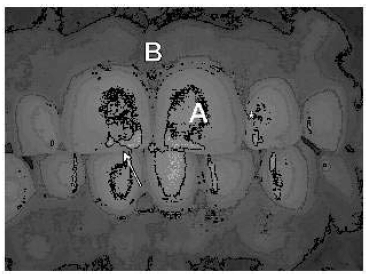

Com base na fotografia clínica frontal mostrada acima, julgue os itens a seguir.

A letra B indica a papila interdental.

Com base na fotografia clínica frontal mostrada acima, julgue os itens a seguir.

A letra A indica a face vestibular do dente decíduo apresentado.